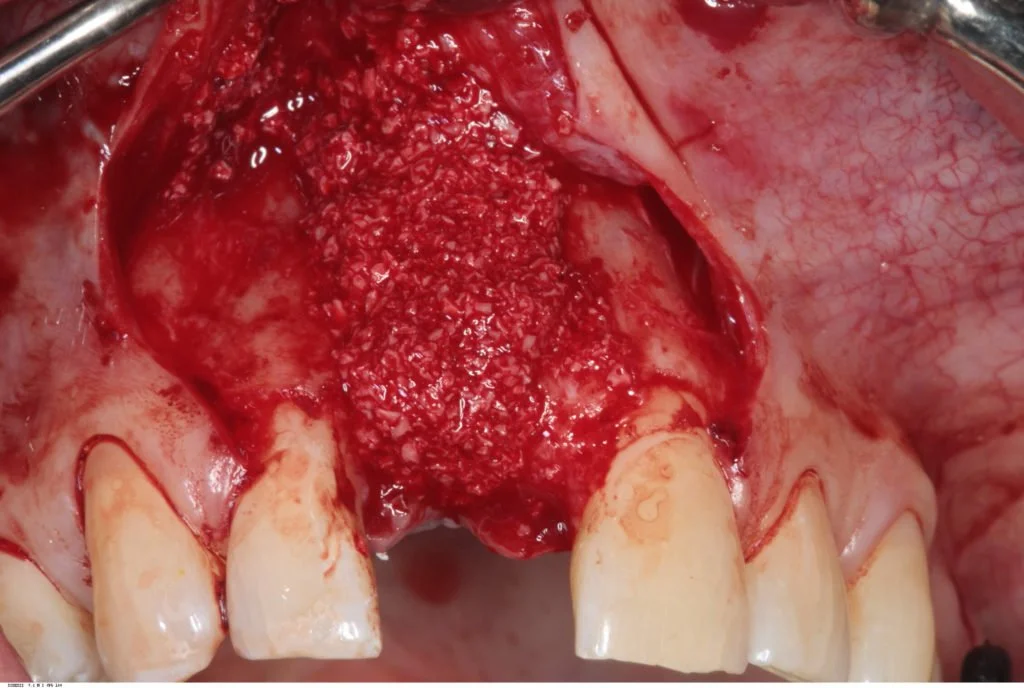

Autogenous bone chips were then harvested from the local area and placed over the exposed implant threads. This was then protected by a layer of Bioss previously mixed with blood, and then two layers of Bioguide.